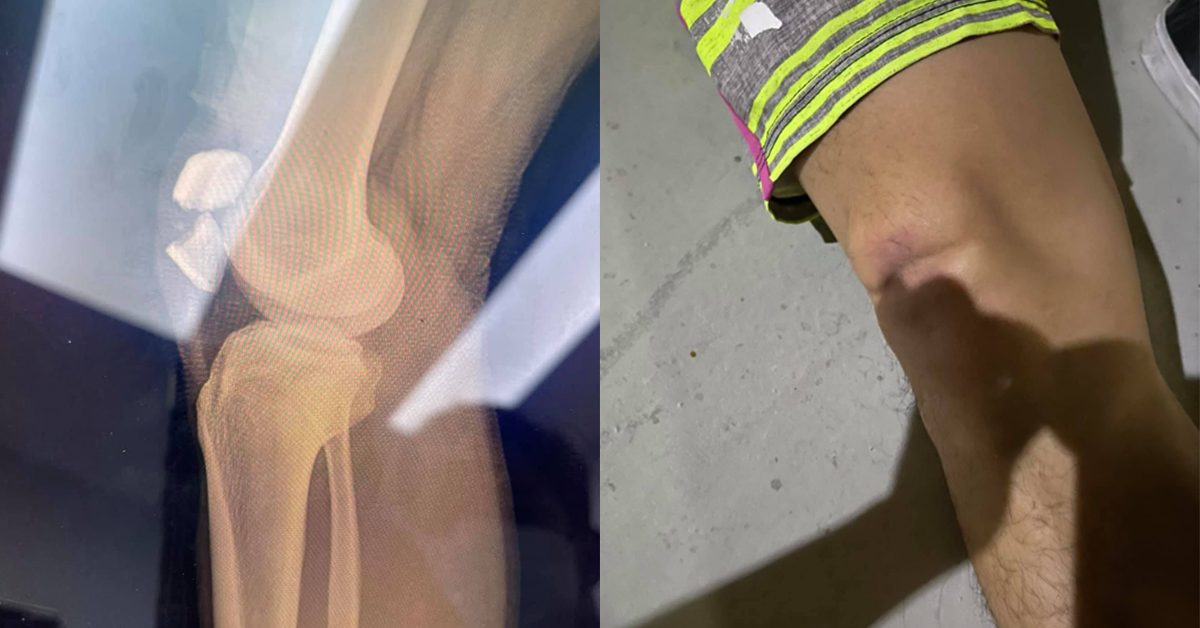

Part1 ณ ที่เกิดเหตุ คนเจ็บเคยเล่นทั้งสเก็ตและเซิร์ฟ ปกติก็ล้มประปรายเวลาแสนป เลยให้ใส่เซฟตี้ แต่ก็ใส่ๆถอดๆ (ผช. ชอบคิดว่าดูอ่อนและไม่เท่ห์ รอบหน้าอยากเท่ห์จะสั่งชุดไอรอนแมนให้ใส่แม่ม!!) ตอนล้มไม่ได้เร็วมากแต่เป็นช่วงกะลังโค้ง นางบิดตัวละบอร์ดพลิก อนิจจัง อนิจจา บอร์ดตั้ง ละล้มหน้าคว่ำหัวเข่าป้าบเข้าให้กับสันอย่างแรง (หมอถามเลยดูจากงานแล้วเหมือนโดนรถชนกระแทกอย่างแรงเลยนะล้มเฉยๆยังงัยก็ไม่ขนาดนี้) อ่ะกลับมาที่เกิดเหตุ เมื่อทุกคนเห็นเข่าเลยไม่ให้ขยับนอนนิ่งไว้ก่อนรอจนรถมูลนิธิมา เค้าตรวจเช็คเบื้องต้นบอกว่าน่าจะแค่หลุดเพราะคนเจ็บไม่ปวดมาก เลยเคใจชื้นนิดนึง

Part3 รพ. ที่รักษาตัวย้ายมาเรียบร้อยรอคุยกับหมอคุยเรื่องคชจ. คร่าวๆ (พนง. แจ้งว่าเบาๆรวมทุกอย่างไม่เกิน 360,000 แน่นอนค่าาา จ้าราคาน่ารัก) เหตุการณ์เกิดห้าทุ่ม ได้ขึ้นห้องตีสี่กว่า ตลอดระยะเวลาคือยังไม่ได้ทำอะไรกับส่วนที่แตกนะคะ จริงๆหมอแจ้งว่า ก็ไม่ถึงกับเป็นเคสผ่าฉุกเฉินรอได้ แค่จะขยับละเจ็บมาก ถ้าได้ผ่าก็จะเจ็บที่แผลแทน ก็เท่ากับว่านอนเล่นรพ. หนึ่งคืนรอหมอมาคุยสิบโมง สรุปคือไม่ได้เปลี่ยนสะบ้า แต่จะใช้น็อตสองตัวยืด และเข้าเฝือกช่วงเข่าไว้แค่นั้น จะได้ผ่าหกโมงเย็นใช้เวลาประมาณชม. ครึ่ง หลังจากนั้นถ้าไม่มีภาวะแทรกซ้อน และฟื้นตัวเร็วสามวันก็อาจกลับได้ แต่ขาก็จะต้องเหยียดตรงอย่างนั้นไปสักระยะ หลังจากนั้นก็ทำกายภาพเอา ต้องคอยขยับให้เลือดหมุนเวียน ใช้เวลาฟื้นตัว3-6 เดือน แต่ส่วนนั้นก็คงไม่ได้ดีเหมือนเดิมร้อยเปอร์เซ็นต์ (แต่ไม่ขาเป๋น้า)